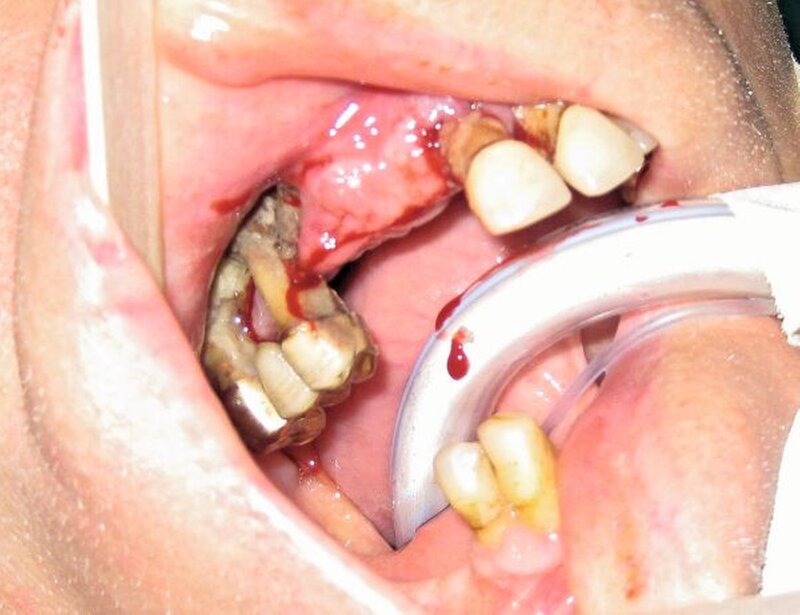

Bei der klinischen Inspektion imponierte ein desolates Gebiss bei starkem Knochenabbau und großflächigem Nekroseareal vestibulär im ersten Quadranten. Die Restbezahnung bestand aus den Zähnen 17, 15, 11 bis 24, 27 sowie 43 und 44. Alle Zähne wiesen Lockerungsgrad III auf. Neben einer spontanen Zahnfleischblutung konnte an mehreren Stellen eine putride Sekretion aus dem Parodontalspalt beobachtet werden. Des Weiteren wies der Patient einen enorm fauligen Foetor ex ore auf.

Als therapeutische Maßnahme erfolgte zunächst unter Intubationsnarkose die Extraktion aller Zähne im Oberkiefer. Hierbei konnte ein großflächiges Knochensequester aus dem ersten Quadranten in toto geborgen werden. Die rechte Kieferhöhle erschien dadurch breitflächig eröffnet, es erfolgte eine ausgiebige Ausräumung des Granulationsgewebes und die Einlage einer Furacintamponade mit Ausleitung zum unteren Nasengang. Der noch verbleibende Alveolarfortsatz des Oberkiefers wurde großflächig dekortiziert, bis sich eine Blutung aus dem Knochen zeigte. Die Deckung erfolgte dann lokal mit Mukoperiostlappen.